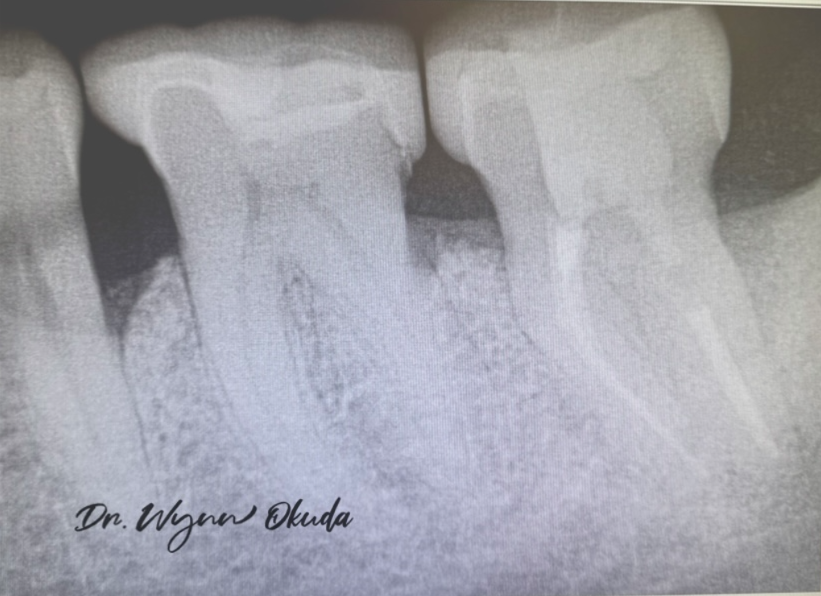

Through minimally invasive surgical technique combined with laser-assisted sterilization, we were able to regenerate bone and preserve what was initially considered a hopeless tooth. Four years post-operatively, the tooth remains stable and fully functional. (Figure 4)

This case reinforced that Waterlase is transformative in regenerative and implant-related procedures.